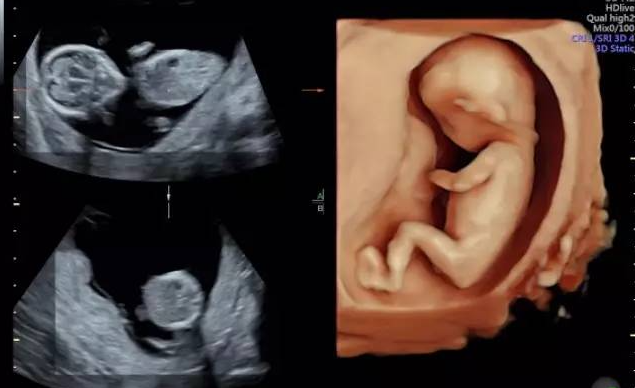

龙港孕妈必看!温州百佳东方四维彩超超全预约攻略!

医院:温州百佳东方妇产医院

地址:温州市鹿城区车站大道79号